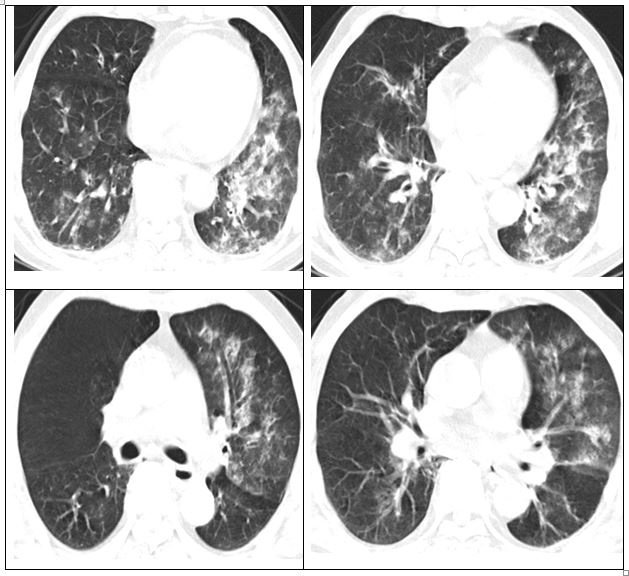

Qua khám lâm sàng, bác sĩ xác định ông C. dương tính cúm A, kết quả CT ngực cho thấy phổi đông đặc, có viêm. Các bác sĩ sử dụng thuốc kháng cúm Oseltamivir cho người bệnh, chống bội nhiễm bằng kháng sinh, thở oxy, khí dung.

Hình ảnh phổi của người bệnh bị viêm lan toả và đông đặc. Ảnh: BVCC.